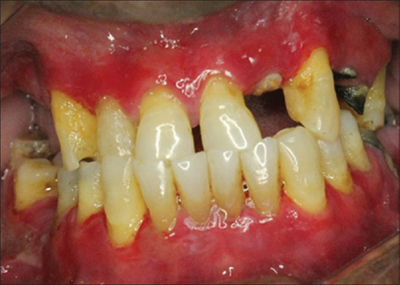

Атрофический вид заболевания слизистой ткани

Возникает из-за плохой гигиены полости рта, в результате чего образуется кариес, налёт, камни, что пагубно действует на состояние дёсен.

Фото 5. Атрофический гингивит десен и полости рта – запущенная форма болезни с паталогическим перерождением эпителиальной ткани.

Отличительная черта такого гингивита – его неизлечимость. Поэтому важно не допустить переход любого воспаления в атрофическую форму.

Все меры лечения атрофического типа гингивита направлены на остановку разрушительного процесса.